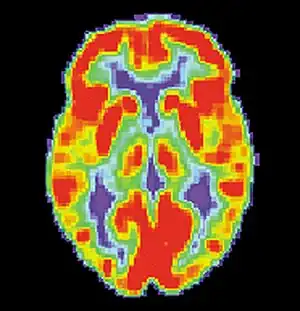

Alzheimer's disease (AD) is a progressive, degenerative and fatal brain disease, in which cell to cell connections in the brain are lost. Alzheimer's disease is the most common form of dementia.[2] Globally approximately 1–5% of the population is affected by Alzheimer's disease.[3] Women are disproportionately affected by Alzheimer's disease. The evidence suggests that women with AD display more severe cognitive impairment relative to age-matched males with AD, as well as a more rapid rate of cognitive decline.[4]

PET scan of a healthy brain - Image courtesy of US National Institute on Aging Alzheimer's Disease Education and Referral Center

PET scan of brain with AD - Image courtesy of US National Institute on Aging Alzheimer's Disease Education and Referral Center